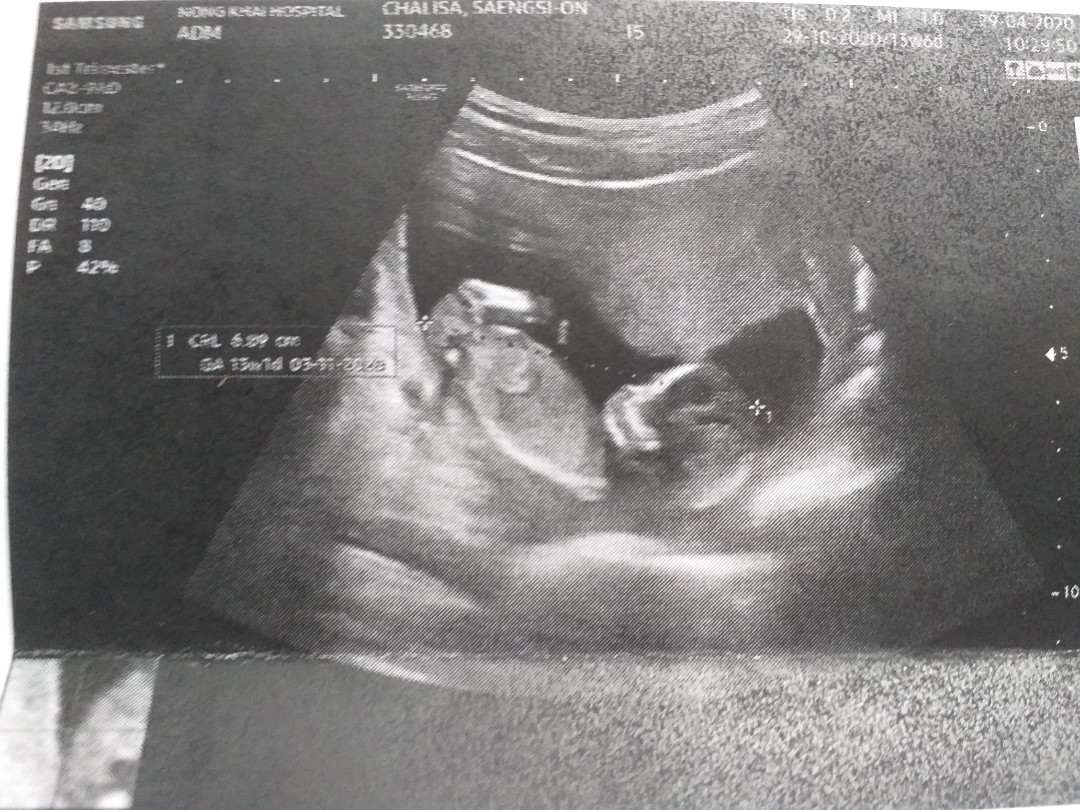

11 สัปดาห์

11 สัปดาห์ ซาวด์มาเจอลูกแบบนี้ถือว่าเขาตัวใหญ่ไหมคะหรือปกติ

ตอน 13 วีคค่ะ